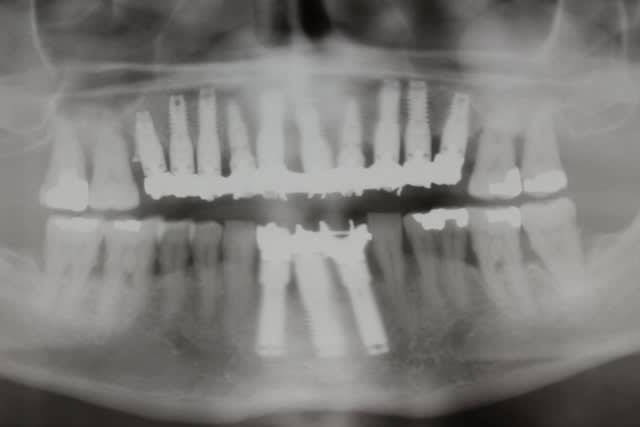

On ne dirait pas la même crête et pourtant il s agit bien de la patiente en préop et 18 mois plus tard...

Quel changement de volume et de qualité tissulaire...

qd tu vois la transformation tissulaire au niveau du volume et de la qualité des muqueuses avant-après, je doute très fort que ce soit une muqueuse diapneusique comme tu le laissais entendre...

A quoi attribues-tu ce changement de volume de tissus ?

C'est uniquement le nanobone ?

J ai placé 2 x 1.2ml et un dernier flacon de 0.6ml

3ml en tout

C est pas un kilo qd même :-)))))))))